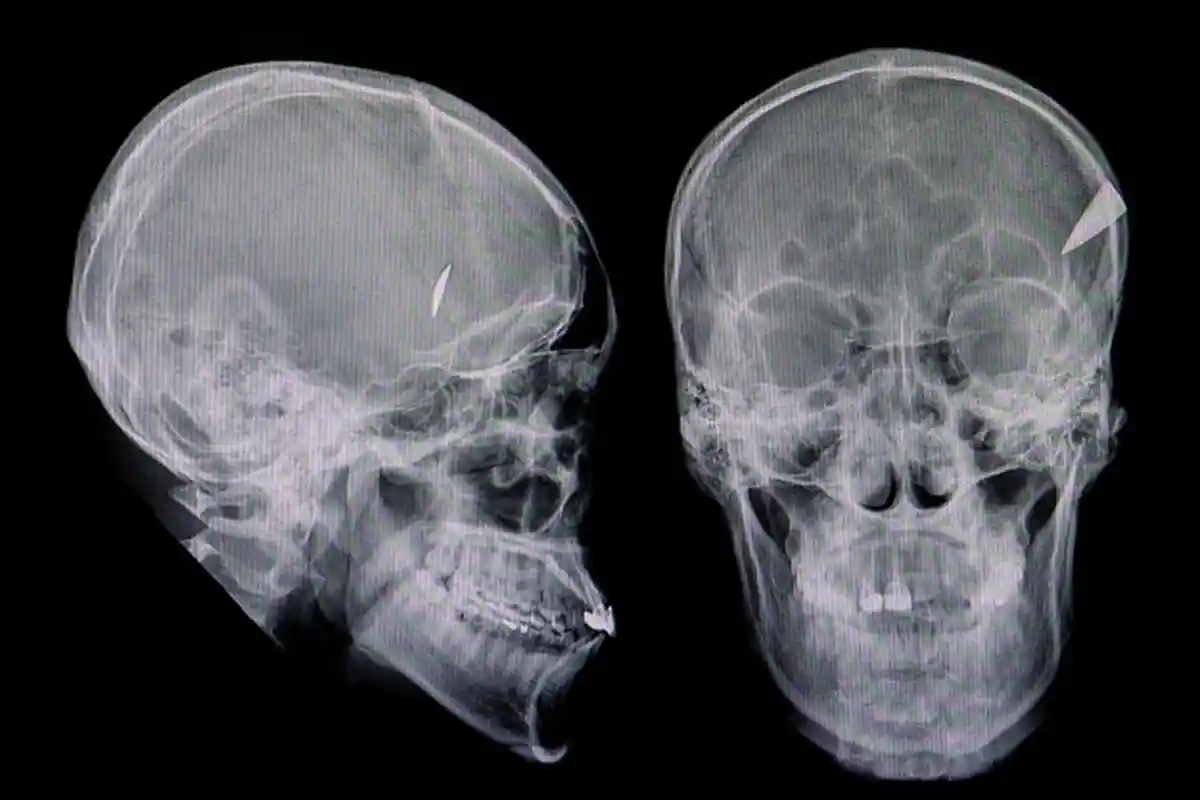

Penyebab dan Gejala Pendarahan Subdural pada Otak, Apa Bahayanya?

Subdural hematoma atau juga disebut perdarahan subdural adalah kondisi ketika darah menumpuk di antara dua lapisan di otak.

Subdural hematoma atau juga disebut perdarahan subdural adalah kondisi ketika darah menumpuk di antara dua lapisan di otak, yaitu lapisan arachnoid dan lapisan dura atau meningeal.